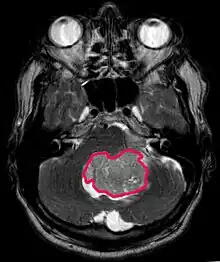

Cette tumeur est typique de la fosse postérieure, où elle est localisée dans les deux hémisphères du cervelet ou dans le vermis cérébelleux. Parce qu'il est envahissant et à croissance rapide, il se propage généralement à d'autres parties du système nerveux central (SNC) via le LCR et peut infiltrer le plancher du quatrième ventricule voisin et les méninges. Plus rarement, des métastases supplémentaires du SNC peuvent survenir. Lorsque la tumeur maligne survient, les symptômes comprennent la perte d'équilibre, l'incoordination, la diplopie, la dysarthrie et l'atteinte du quatrième ventricule, ce qui entraîne souvent une hydrocéphalie obstructive, des maux de tête, des nausées et des vomissements et une démarche instable.

L'IRM montre généralement une lésion de contraste massive impliquant le cervelet. Comme mentionné ci-dessus, le médulloblastome a une forte propension à infiltrer localement les leptoméninges ainsi qu'à se propager à travers l'espace sous-arachnoïdien, impliquant les ventricules, la convexité cérébrale et les surfaces leptoméningées de la colonne vertébrale. Par conséquent, il est nécessaire de mettre en résonance tout l'axe crânio-spinal.

Le but de la chirurgie est d'enlever autant que possible la masse présentée par la lésion. En effet, les tumeurs résiduelles postopératoires entraînent un moins bon pronostic. La présence de cellules tumorales dans le liquide céphalo-rachidien ou la détection par résonance de métastases leptoméningées est également un signe avant-coureur d'un pronostic défavorable. La chirurgie seule n'est généralement pas curative. Dans certains cas, cependant, une irradiation thérapeutique de l'axe craniospinal, focalisée sur le site tumoral primaire, peut en résulter. L'ajout d'une chimiothérapie après la radiothérapie augmente le taux de guérison. Des médicaments à base de platine (cisplatine ou carboplatine), de l'étoposide et un agent alkylant (cyclophosphamide ou lomustine) sont utilisés avec la vincristine. Avec un traitement approprié, les cas de longue survie de plus de 3 ans chez les patients atteints de médulloblastome varient de 60 à 60 ans et 80 Pour cent.